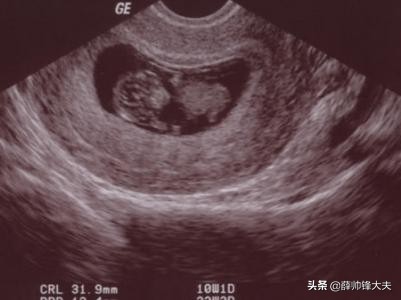

对于月经周期正常的女性,停经六周(也就是42天)左右,可以通过经阴道超声看到原始心管搏动。如果按照同房时间算的话,应该是同房后四周左右能看到胚胎的原始心管搏动。

用末次月经的第一天开始计算,最早35天左右,做阴式彩超就可以看到胎心,一些人可能会晚几天,42天100%能看到,除非月经周期长或者月经不规律。

很多人不喜欢做阴式彩超,腹式彩超清晰度差一点,所以腹式彩超要晚一点发现胎芽胎心。一般需要停经40天左右,个别人可能再延长一周。

怀孕多长时间可以用B超查出有没有胎心,这个需要根据不同B超分别对待,阴道B超较腹部B超可以更早的发现胎心,但是国人往往对阴道B超存在敌意,一般做的都是腹超,腹部B超一般在孕5周是出现孕囊,孕6周左右出现胚芽及心搏,晚点的需要孕7-8周。这个具体存在差异性,尤其是那些月经不规则的宝妈们,正常情况下孕囊出现后2-3周出现心搏,不能按常规的停经时间计算。